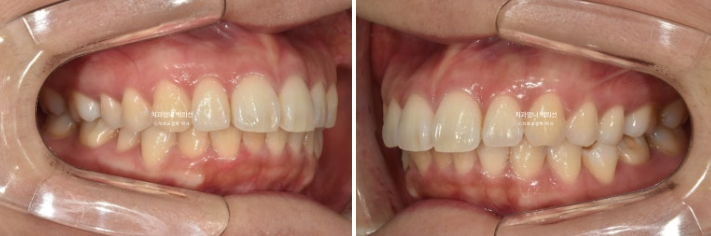

22.09~25.04